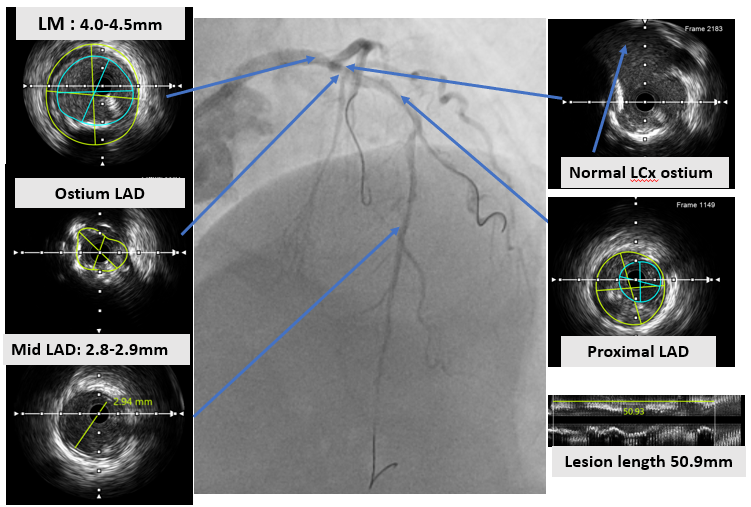

An ultra low contrast PCI of the LAD was performed using dual puncture with EBU 3.5/7F and JR 3.5/6F catheters via radial and femoral access. Saline was used for engagement, with contrast restricted to microcatheter injections of 1 cc each as a sparing strategy. Antegrade proximal cap puncture with Finecross and Fielder XTA tracked subintimally, and a parallel wire technique with Gaia Next 2 successfully crossed the lesion, confirmed by retrograde injection. Lesion preparation was achieved with a semicompliant balloon (2.5 ¡¿ 15 mm) from mid to proximal LAD and a cutting balloon (2.75 ¡¿ 18 mm) from mid to ostium LAD. IVUS pullback revealed a long diffuse lesion with proximal and ostial calcification, showing calcium cracks after preparation. MLA at the ostium LAD was 2.5 mm©÷, distal reference diameter 2.8 mm, and LM diameter 4.5 mm. Stent deployment was guided by multiple wires as anatomical landmarks without contrast. A DES (3.5 ¡¿ 28 mm) was implanted from distal LM crossover to proximal LAD, followed by POT with a 4.0 ¡¿ 9 mm NC balloon. A second DES (2.75 ¡¿ 28 mm) was placed in proximal to mid LAD overlapping the first, with post-dilation using a 3.0 ¡¿ 15 mm NC balloon. IVUS confirmed well-expanded, well-apposed stents without edge dissection. Final MSA was 12 mm©÷ in LM, 10.8 mm©÷ in ostium LAD, and 6.3 mm©÷ in mid LAD. Final angiography with diluted contrast demonstrated TIMI 3 flow, with total contrast use limited to 12 cc.